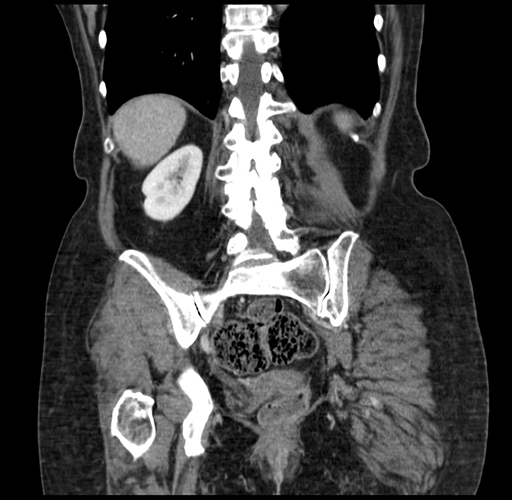

Pre-Chemo: Coronal Venous

Coronal Venous